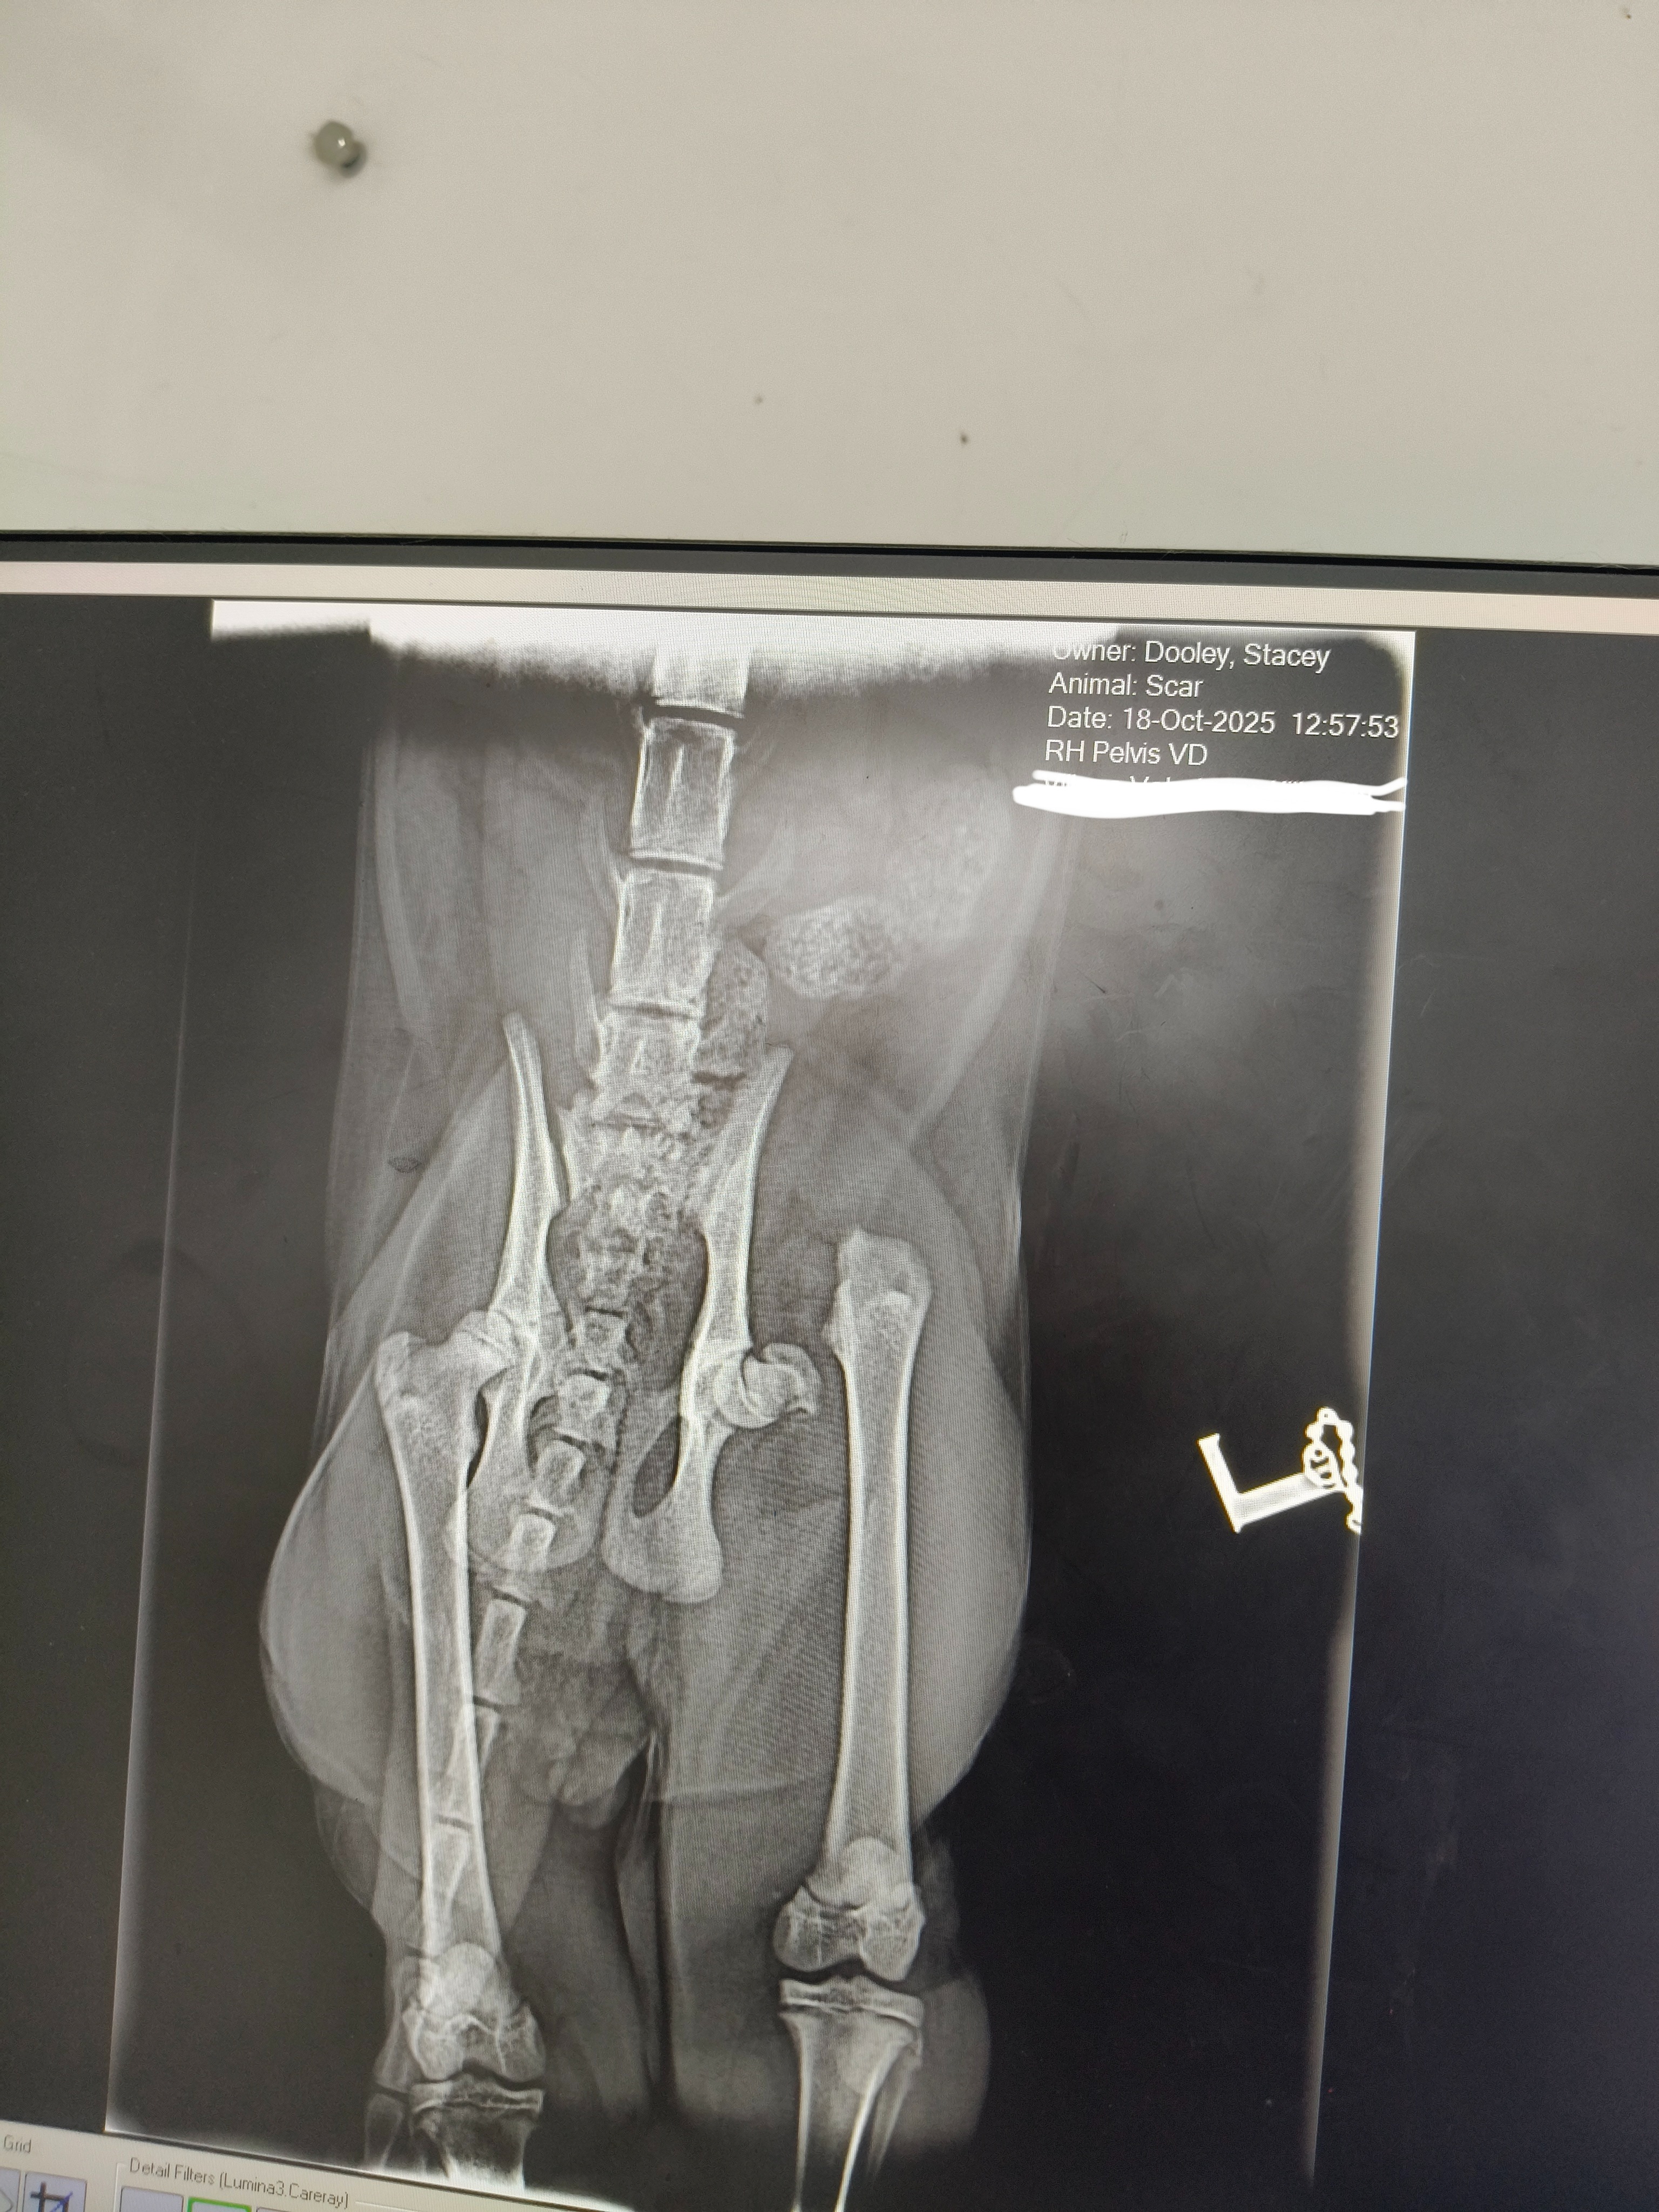

On Saturday 18 October, he came into me in the early hours dragging his back leg and wailing in pain. After a trip to the vet (and a mild heart attack on my part), I found out he’s fractured his hip near the joint. The surgery he needs is called an FHO. This is basically where they remove the ball part of the hip so his body can create a “false joint.” The good news: young cats often adapt brilliantly. The bad news: I need to find the money to actually do it